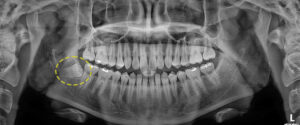

먼저 첫 번째 소개해 드릴 환자분은

다행히 하악 우측에만 사랑니를

가지고 계셨는데요.

잇몸 안쪽이 간헐적으로 부어서

본 원에 내원해 주셨어요.

육안으로 보기에도 잇몸이 부어있던 상태라

정확한 판단을 위해 파노라마와

CT 촬영을 해보았어요.

환자분의 경우 수평 매복 되어 발치 난이도는

높았지만 다행히 신경관과 맞물려 있는

상태는 아니였어요.